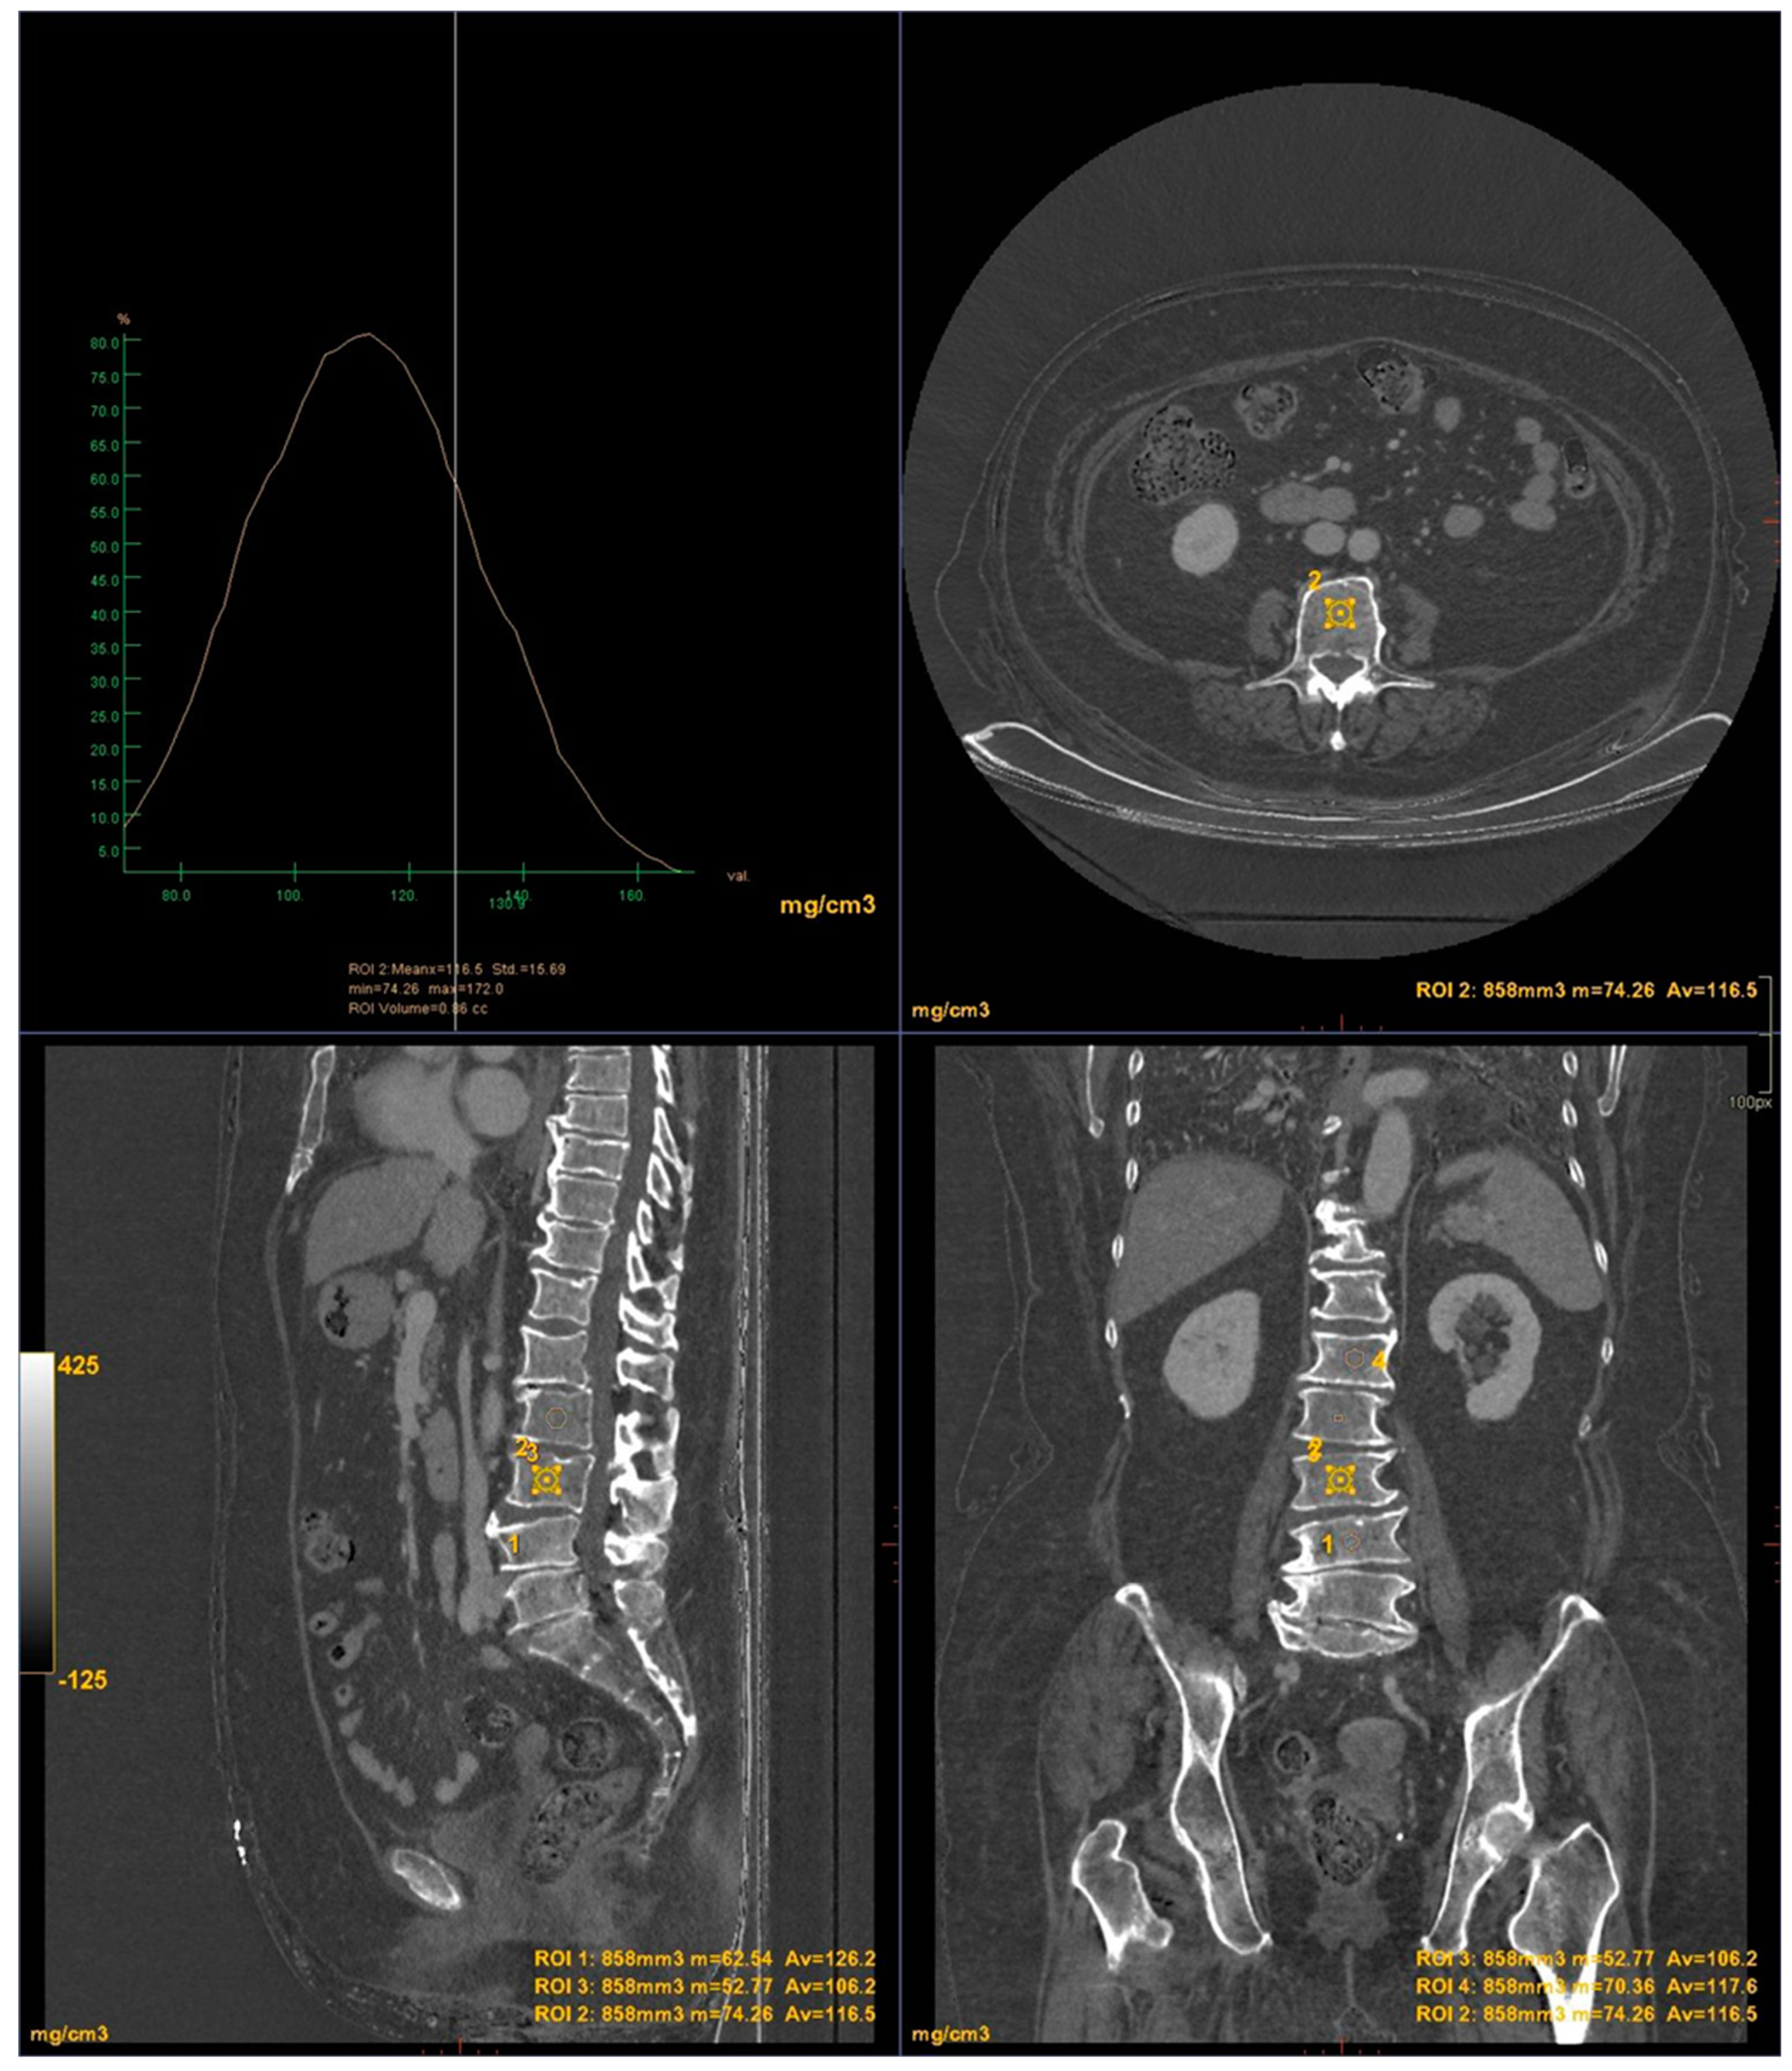

All images were acquired using a 256-slice multidetector CT system with spectral imaging capability (Revolution, GE Healthcare, Chicago, USA) using a 1.0 mm slice thickness, tube voltage of 80-140 kVp, and tube current of 200 mA (Dose Right automatic exposure control system). The CT data were reconstructed with GSI data, and MPR reconstructions were performed in coronal and sagittal planes. DXA scans were performed using a bone densitometer (Discovery A, HOLOGIC, USA) for the lumbar vertebrae (L1 to L4) and femoral neck (Figure 1 and Figure 2).

CT images were processed using AW3.2 software (GE Healthcare, USA) with a bone window and HAP(fat) reconstruction filter, which highlights structures containing hydroxyapatite. Three-dimensional volume of interest (VOI) measurements were taken at the lumbar vertebrae (Figure 3) and femoral neck (Figure 4), sampling the trabecular bone while excluding cortical bone regions.

Figure 1. DXA measurements on the lumbar vertebrae.

Figure 3. DECT measurements on the lumbar vertebrae.

For the lumbar vertebrae the mean BMD and T-score on DXA images were 0.648 g/cm2 and -3.66 for the osteoporosis group, 0.855 g/cm2 and -1.73 for the osteopenic group and 1.02 g/cm2 and -0.83 for the normal group, respectively (Figure 5). There was a significant difference among the osteoporosis, osteopenic and normal groups in BMD and T-score (all p < 0.001). The mean HAP value on DECT images was 144.86 mg/cm3 for the osteoporosis group, 162.49 mg/cm3 for the osteopenic group and 139.57 mg/cm3 for the normal group (p= 0.2591) (Table 1). Bland-Altman analysis revealed a bias of 0.09, with 95% limits of agreement from −1.6 to 1.8 (p = 0.4) (Figure 6).